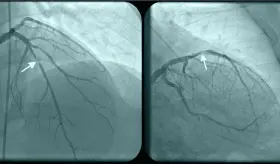

La compresión de la arteria coronaria principal izquierda (LMCA) por dilatación de la arteria pulmonar representa una complicación subdiagnosticada de la hipertensión pulmonar severa, con prevalencia del 6%.